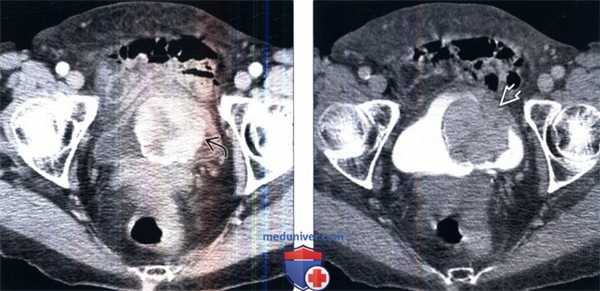

(Справа) КТ с контрастированием, аксиальный срез: у этого же пациента определяется прерывистое контрастирование объемною образования. Околопузырная жировая клетчатка, прилегающая к образованию, не имеет четких границ, что позволяет предположить пристеночное распространение этого процесса. (Слева) КТ с контрастированием, более каудальный аксиальный срез: у этого же пациента определяется прерывистое контрастирование объемного образования с зоной центрального некроза.

(Справа) КТ с контрастированием в отсроченную фазу: у этого же пациента определяется полипоидное образование в виде дефекта наполнения в констрастируемой моче. Отмечается наличие широкого основания, которым образование прикрепляется к стенке мочевого пузыря. При хирургическом вмешательстве эту опухоль было очень трудно удалить. По данным исследования замороженного среза была предположена саркома, однако окончательным диагнозом стала воспалительная псевдоопухоль мочевою пузыря.

(Слева) КТ с контрастированием, более каудальный аксиальный срез: у этого же пациента определяется прерывистое контрастирование объемного образования с зоной центрального некроза.